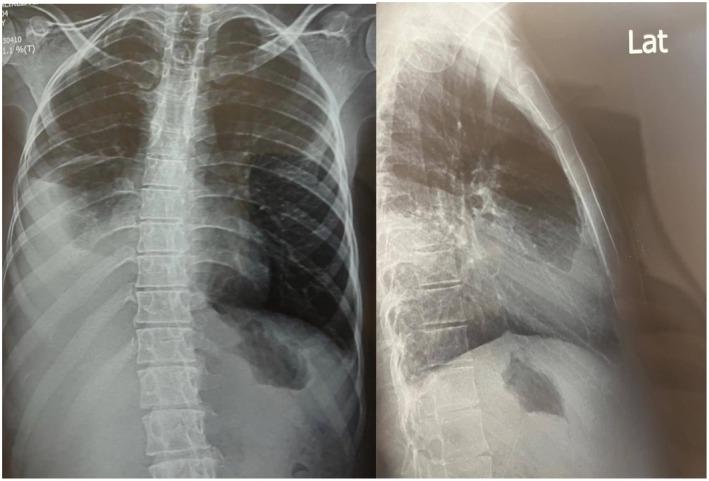

Graft-versus-host disease (GVHD) is a serious inflammatory complication that can arise after allogeneic transplantation, characterized by donor T-cells attacking the recipient's tissues. While cardiac complications are infrequent, they are more commonly observed in cases of chronic GVHD and may manifest as pericardial effusion, cardiac tamponade, and various arrhythmias. Additionally, chronic GVHD can result in constrictive pericarditis (CP) due to the accumulation of fluid and scarring. A 25-year-old Iranian man developed CP 14 years after undergoing allogenic stem cell transplantation. Following inadequate response to medical therapy, he underwent a pericardiectomy. Pathological examination during follow-up revealed fibrosis and mild chronic inflammation. This report aims to add another case of cardiac manifestation associated with GVHD to the current literature. The main message emphasizes the urgent need for prompt diagnosis and effective pericardiectomy, which can be life-saving. Surgical referral should always be an option, and post-operative immunomodulation is crucial.

移植物抗宿主病(GVHD)是同种异体移植后可能出现的一种严重炎症并发症,其特征是供体T细胞攻击受体组织。虽然心脏并发症并不常见,但在慢性GVHD病例中更常观察到,可能表现为心包积液、心脏压塞和各种心律失常。此外,慢性GVHD可因液体积聚和瘢痕形成导致缩窄性心包炎(CP)。一名25岁的伊朗男子在接受异基因干细胞移植14年后患上了CP。在对药物治疗反应不佳后,他接受了心包切除术。随访期间的病理检查显示有纤维化和轻度慢性炎症。本报告旨在为当前文献增加另一例与GVHD相关的心脏表现病例。主要信息强调迫切需要及时诊断和进行有效的心包切除术,这可能挽救生命。手术转诊应始终是一种选择,术后免疫调节至关重要。